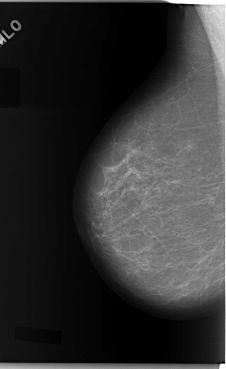

C_0081_1.RIGHT_MLO

LEFT_MLO LINES 5904 PIXELS_PER_LINE 3768 BITS_PER_PIXEL 12 RESOLUTION 50 OVERLAY

FILE: C_0081_1.LEFT_MLO.OVERLAY

TOTAL_ABNORMALITIES 1

ABNORMALITY 1

LESION_TYPE MASS SHAPE IRREGULAR MARGINS SPICULATED

ASSESSMENT 5

SUBTLETY 5

PATHOLOGY MALIGNANT

TOTAL_OUTLINES 1

BOUNDARY